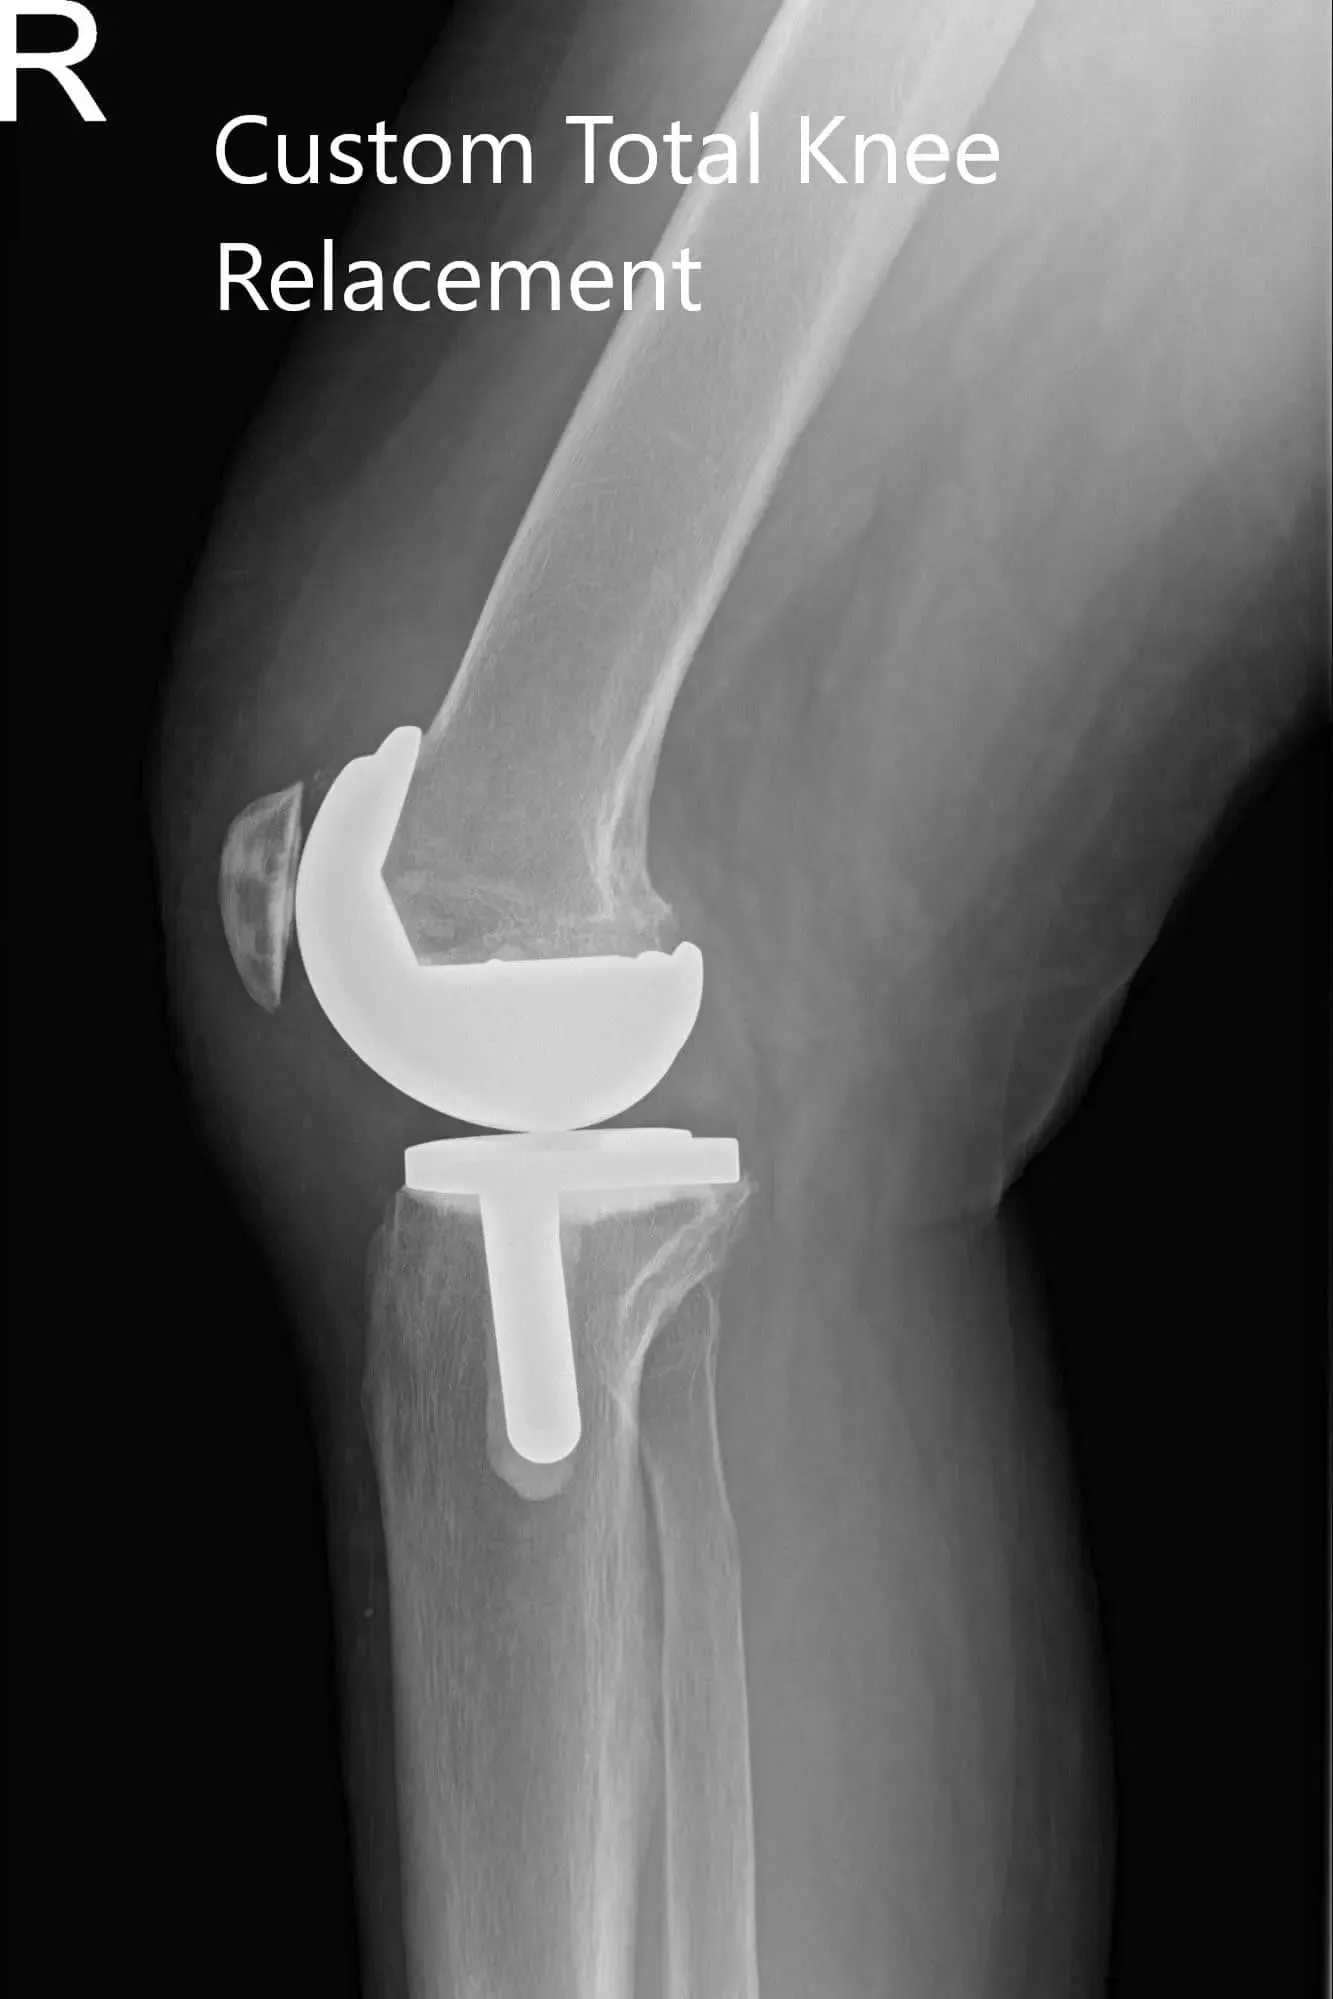

El implante utilizado: Implante femoral personalizado con una bandeja tibial personalizada con inserto de polietileno de 6 mm y rótula de 32 mm x 8,5 mm.

Radiografía postoperatoria del paciente que mostró visión AP y lateral de la rodilla derecha